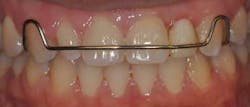

The first step to the successful, long-term management of a congenitally missing lateral incisor case is early detection and referral to the orthodontist. The role of the orthodontist in the early mixed-dentition stage of development is to monitor and guide the eruption of the permanent canine. If the crown of the permanent canine is erupting apical to the primary canine root as it normally does, it may be necessary to selectively extract the primary lateral incisor to encourage the permanent canine to erupt adjacent to the central incisor. The reason for this is twofold. A mesially positioned canine not only provides a natural means for augmenting the supporting tissues, but it also allows for greater flexibility in future treatment planning.

An absence of a permanent lateral incisor will result in restricted growth of the alveolar ridge in the buccolingual dimension, since the only source of development will be from the narrow root of the deciduous lateral incisor. On the other hand, if the orthodontist can manipulate the much larger permanent canine to erupt mesially through the alveolar ridge, its larger root will naturally develop a much thicker buccolingual dimension to the alveolar ridge. Once the canine has erupted, the orthodontist then has the option to distalize the canine into its natural position, leaving behind an augmented ridge. (6,7) Recent studies have shown that space opened orthodontically should remain stable over time (resorption rate of 1% over four years) and may eliminate the need for an additional surgical procedure for alveolar augmentation in the future. (3) This stability is particularly beneficial for implant treatment since fixture placement cannot occur until facial growth is complete. Regardless of whether the definitive restoration is to be an implant or a fixed partial denture or even a removable prosthesis, the esthetics will be vastly improved by this augmentation.

of site development and was later distalized with the aid of orthodontics.

The ridge was significantly augmented but the patient will still likely need

additional grafting at the time of implant placement.

(Photos courtesy of Dr. Kevin Race)